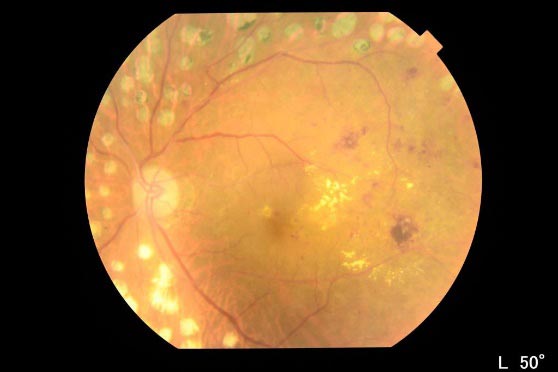

単純網膜症

網膜の血管の状態が悪くなると、血管から血液の成分が血管外に漏れ出します。網膜の中心である黄斑部似血液の成分が漏れて貯まると、黄斑浮腫と呼ばれる状態になり、視力が大幅に低下し、ものが歪んで見える(変視症)という症状を来します。逆に黄斑浮腫が出ない場合は、自覚症状が現れにくいです。それでも網膜の毛細血管で糖がだぶつき、これによって同血管が詰まるなどすれば、新生血管が発生し、この脆くて破れやすい血管から血液の成分が漏れる、硝子体内に出血するとなると、飛蚊症(虫が目の前で飛んでいるように見える)、視力低下、霧視などの症状がみられるようになります。さらに放置を続けると網膜表面に増殖膜が張ってきて、網膜剥離を起こし、失明することもあるので要注意です。

診断をつけるための検査としては、主に眼底検査によって、網膜の状態や出血の有無、硬性白斑、新生血管を調べるなどして、判定していきます。